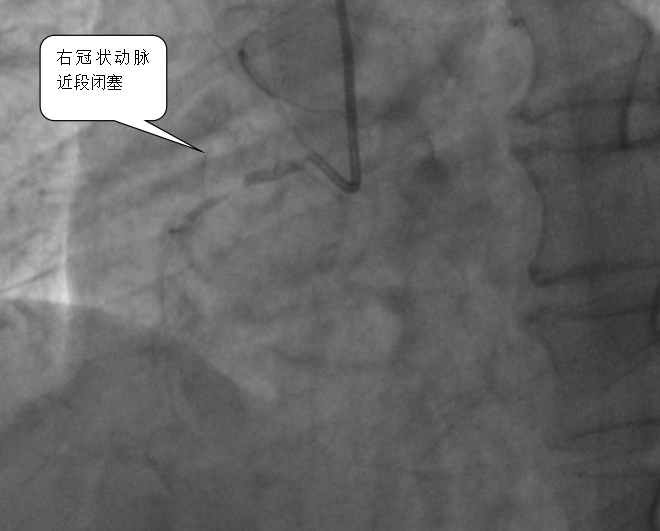

医院心血管内科专家团队立即启动胸痛中心绿色通道,从患者入院到完成心电图检查仅用3分钟,确诊后2分钟内即给予抗血小板治疗,并紧急实施冠脉介入手术。术中造影发现患者右冠状动脉近段完全闭塞,医生通过血栓抽吸、冠脉内溶栓及药物球囊扩张等操作,最终成功植入支架,恢复血流。术后患者血压、心率恢复正常,转危为安。